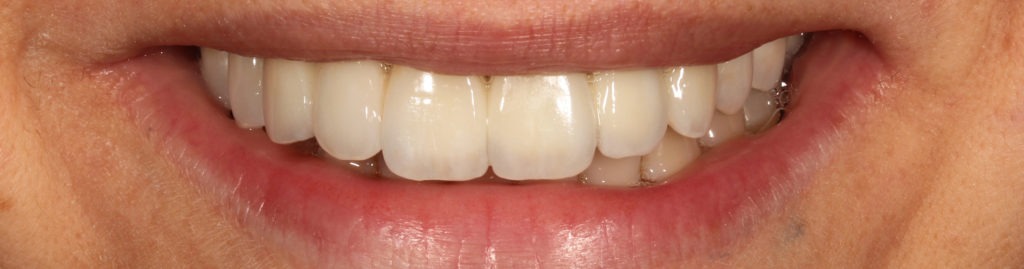

Casos clínicos de éxito

Hemos rehabilitado con éxito a decenas de pacientes que, tras años con prótesis removibles o sin soluciones viables, han logrado volver a sonreír y comer con confianza gracias a esta técnica revolucionaria. Nuestros resultados clínicos están avalados por fotografías, testimonios y seguimientos a largo plazo.

Ver más sobre este caso de éxito